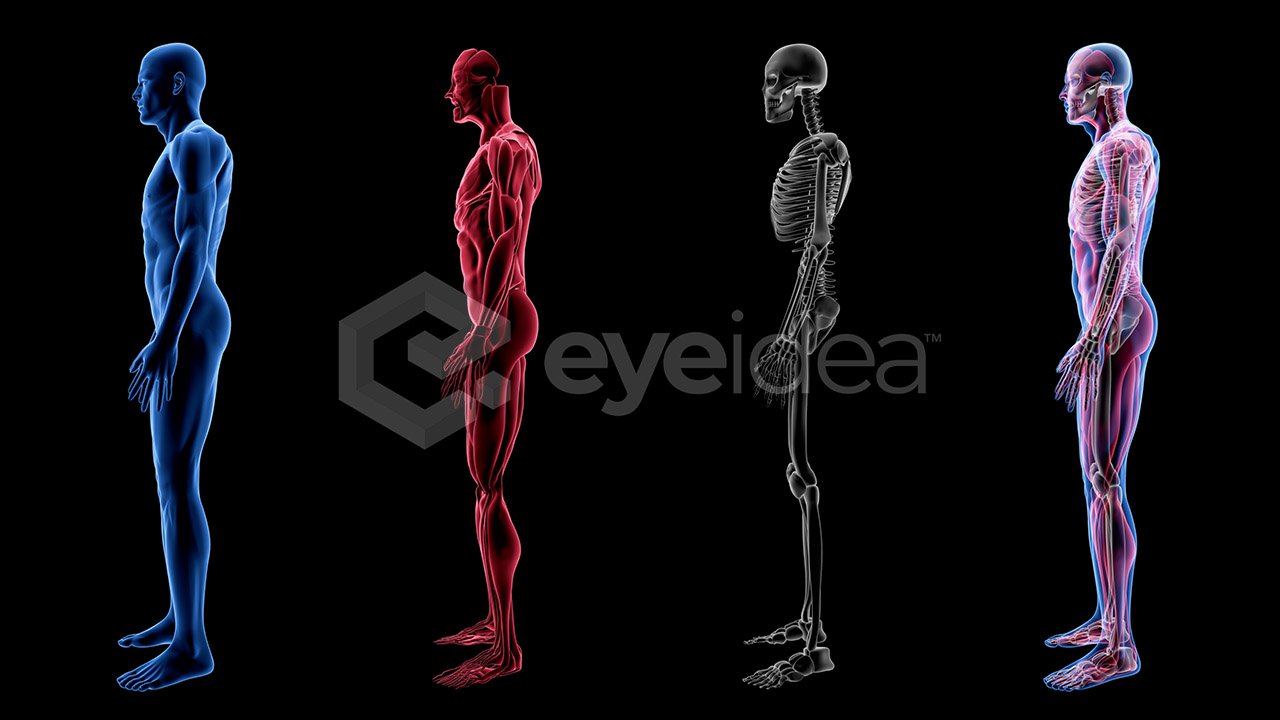

Made by Professionals

Our stock videos, images, and animations come

with a wealth of experience spanning over two

decades, giving creators assurance

of premium quality assets.